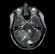

Photon-counting computed tomography (PCCT) promises to revolutionise CT imaging by substantially increasing spatial resolution and iodine contrast conspicuity, reducing radiation dose and beam hardening artifacts, and allowing spectral imaging with multiple energy bins.

Unlike traditional energy integrating detectors which use solid-state scintillators to first convert X-ray photons to light, photon-counting detectors use a semiconductor material to directly convert incoming X-rays to an electric signal in a single step. Each photon gives rise to a voltage that is proportional to its energy, allowing energy discrimination on the basis of voltage comparison. A count can therefore be assigned to the bin that matches the photon’s energy range, hence the name “photon counting”. With enough bins, one can therefore perform spectral analysis of the incoming photon flux, and extract spectral information for quantitation or material decomposition. Since lower energy photons, which produce more contrast information, get equal weighting to higher energy ones, the images have improved contrast resolution.

Prof Roland Bammer, Head of Monash University’s Department of Imaging*, describes this transition. “Remember the times when you were watching sports on a low-res black and white TV with the “bunny ears” on top? Now you can watch events in colour on your 4K TV. This is the paradigm shift in CT that’s currently happening with photoncounting. The ‘colour’ depth isn’t OLED quality yet, and more like on the old CGA or VGA monitors, but it’s there. You can do all the interesting things energy integrators can’t do without dual kV source or kV switching. PCCT does the energy discrimination on the

detector side, and opens up a new field in radiology.”

Although it has long been known that photon counting is the most efficient approach to X-ray detection for CT, developing a direct conversion material which can handle the high X-ray photon flux of CT has been the major challenge. Prof Bammer says “Whether the future of photon-counting CT will lie in cadmium telluride (CdTe), cadmium zinc telluride (CZT), or silicon (Si) semiconductors is still unclear. The jury is still out. The individual vendors seem to have made bets on different semis. Each material has its strengths and weaknesses, and the vendors have learned to leverage the strengths of their material and minimise the impact of its weaknesses. The upcoming RSNA will therefore be very interesting. We might see more vendors entering this space. I believe independent research— outside the corporate labs—is warranted to get to the bottom of it. Once more systems are installed, it will help us to provide the evidence base on real-world performance in clinical settings. Whether it’s the more difficult to manufacture but highly efficient CdTe semis, or the more broadly available, cheaper silicon substrate, is superior, of one thing I am confident: we will see a lot of innovation and new clinical applications in that space in the near future. It’s another big fork in the road for CT, similar to when spiral or multi-detector row CT were introduced. I am therefore very excited about this technology.”

Physicist Dr Christian Schroeter, PhD, who led the effort to develop the direct conversion detector material for Siemens Healthineers, talks to Associate Professor Shalini Amukotuwa, PhD, MB BS, FRANZCR (Head of Diagnostic Neuroradiology and MSK at Monash Health) about the detector and his experience in developing it.

Photon-counting detectors have brought about a paradigm shift in CT imaging. Can you tell us what the main advantages of this technology are, compared to the conventional CT scanners which we are currently using?

There are several technical advantages: higher spatial resolution, elimination of electronic noise, radiation dose efficiency and, last but not least, spectral information, not only in every image, but also everywhere in the image. Improvement in these crucial technical parameters translates to clinical benefits, which we have been working on since the prototype phase. We have already seen that there are certain things that you can only do with a photoncounting CT. For example, a really hot topic is imaging stented coronary arteries. The metallic stents cause a lot of artifacts, due to beam hardening and photon starvation, which obscure the vessel lumen. These patients are therefore often sent to cathlab instead

of CT coronary angiography. Now, with photon-counting CT, we can get really good images of the vessel lumen, to see in-stent details. This is because of the far superior spatial resolution, reduced blooming and beam hardening, and lack of electronic noise, which we can filter out. The spectral information also allows us to obtain material (iodine) images of the vessel lumen, and we can use material decomposition to subtract out any calcified plaques. We are currently exploring whether these images are now accurate enough for catheter angio to be avoided, which will be a big game changer for patients. Another important example is imaging obese patients, and low-dose imaging, where photon counting provides better image quality with less noise because electronic noise is eliminated. The journey has only just begun, and we will continue to see what these technical advantages really mean in clinical practice, since that’s what’s important.

Why did it take so long to develop photon-counting CT scanners? What was the main barrier to overcome?

The direct conversion material for the detector was the main barrier, and we had a long development phase. The project started 20 years ago. We seriously engaged in screening the market of available detector materials around 15 years ago. The first phase was to look at what was already available, then select the best vendor. We identified a company in Japan

The main challenge at that time, 15 years ago, was that most manufacturers used the detector material for gamma cameras, for SPECT, or just spectrometers. The company that we selected already used CdTe detector material for X-ray imaging, although this has a much lower X-ray photon flux than CT. Of all imaging applications, CT has by far the highest X-ray photon flux applied to the detector. The materials which were available then just couldn’t cope with this high flux. There were even scientific papers claiming, based on models, that it may not be possible for CdTe detectors to convert X-rays to photons directly at the typical flux-rates of CT. In the initial prototypes, we could slow down the flux to address this. However, for a clinical full body scanner, you need to be able to work at high flux rates, to be able to deal with any clinical scenario. We were lucky that we came to a point, around 2011, where we could overcome this apparent fundamental hurdle and major impediment which otherwise would have put an end to the project. Another group did actually give

Yes. The solution was based in the CdTe crystal growth itself. You have to go very deep into the very start of the process chain, to the crystal itself, to address the problem of polarisation. You need to understand the whole chain, from crystal growth to image generation, and we saw that many aspects of the crystal growth, for example doping (where tiny amounts of impurities are introduced to alter the crystal structure), the temperature treatment, and the electrodes that we applied, needed to match the bulk material. We had to bring all these pieces together, and understand the signal that comes out of the detector material to design the electronics, the application specific integrated circuit, accordingly. But the trick was really in the first steps, and it was quite a basic one.

Volume 18 No 4 | September 2022 19

So those steps reduced the amount of charge (hole) trapping in the detector material, which is the cause of depolarisation?

Yes. The assumptions, which were made in the models which showed that building a CT detector from CdTe would not be possible, were not as simple as initially thought. The models that we now have, based on our empiric observations and better understanding of the detector material, are quite different. It turns out that hole trapping is not such an issue after all! In fact, it never was a fundamental issue for CdTe, but back then, we didn’t have the knowledge and understanding to have this insight and confidence. Now, the fact that there is a clinical whole-body photon-counting CT shows that the argument that CdTe can’t be used as a detector just doesn’t hold true. We have also seen that there is another company in Canada which is stepping into prototyping at a clinical level using a detector with similar material, CZT. I’m therefore confident that they have also overcome this basic hurdle.

Can silicon detectors work for photon-counting CT?

Spatial resolution is the major weakness of silicon-based detectors, and also radiation dose efficiency because of lower absorption which is due to the lower atomic number. With any detector material, you can, with the right system design, bring out one specific parameter and excel at it. For example, extremely high spatial resolution, energy resolution, or dose efficiency. That is nice for a scientific paper or a prototype, but not for a clinical product. You need to have a holistic approach, and bring together and harmonise these parameters for a clinical scanner. You also need scan speed, which is underestimated, and not just for cardiac applications. Dose efficiency and spatial resolution maybe the most important, but then speed, and then energy information. We worked on this integration and harmonisation for 10 years, starting with prototypes scanners and ending with the final product. In my understanding and firm opinion, silicon just can’t do this.

Do you need more than four energy bins?

We will see. It felt like the end of the journey when we launched the clinical scanner, now it seems like it’s just the beginning. We will see what the clinicians and researchers will find out. But right now, in my opinion, even if you have one threshold, you already have most of the advantages of photon counting, like dose efficiency, high spatial resolution, and absence of electronic noise. If you have two energy bins, you can do iodine separation. With a third bin, then you can do crazy stuff, with new contrast agents such as gadolinium and gold particles, which have a k-edge. It is possible then to make an additional energy separation, but this is a very early, pre-development research topic. The scanner has a fourth bin, so you are future proof in case somebody invents something where you need it. More bins than that are superfluous.